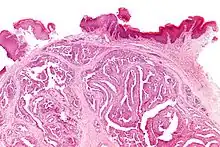

| Micrograph of a papillary hidradenoma with papillary structures; fragmented overlying epidermis is at the top of the image. H&E stain. | |

Microscopic histopathological analyses of papillary hidradenoma tumors typically reveal a nodule in the dermis, i.e. layer of skin between the epidermis and subcutaneous tissue. The tumor consists of complex patterns of interconnecting tubular and papillary (i.e. thin finger-like or frond-like) structures.[19] These structures are lined with glandular epithelial and myoepithelial cells. The glandular epithelial cells appear to be excessively proliferating in the ducts leading to the epidermis and show oxyphilic changes, (i.e. cytoplasm filled with large mitochondria, glycogen, and ribosomes) while the myoepithelial cells often appear clear cell-like, i.e. have uncolored cytoplasm when stained with hematoxylin and eosin.[1] The histopathology of anogenital and ectopic papillary hidradenomas are similar to each other.[7][9][15][18]